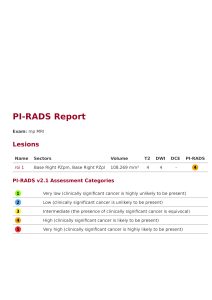

Η περαιτέρω χρήση από το διαγνωστικό μας κέντρο του λογισμικού της Advantis Brainance MD, μας δίνει τη δυνατότητα να εντοπίζουμε ακόμα μικρότερες ύποπτες εστίες, να μελετάμε την αιμοδυναμική τους συμπεριφορά και να αναλύουμε σημαντικές παραμέτρους με στόχο την ακριβέστερη ταξινόμηση των ύποπτων περιοχών κατά TI-RADS. Επισυνάπτεται δε, στον κλινικό ιατρό, λεπτομερής τοπογραφική παρουσίαση των ύποπτων εστιών, με στόχο τον ακριβέστερο προσδιορισμό του σημείου / των σημείων της βιοψίας.